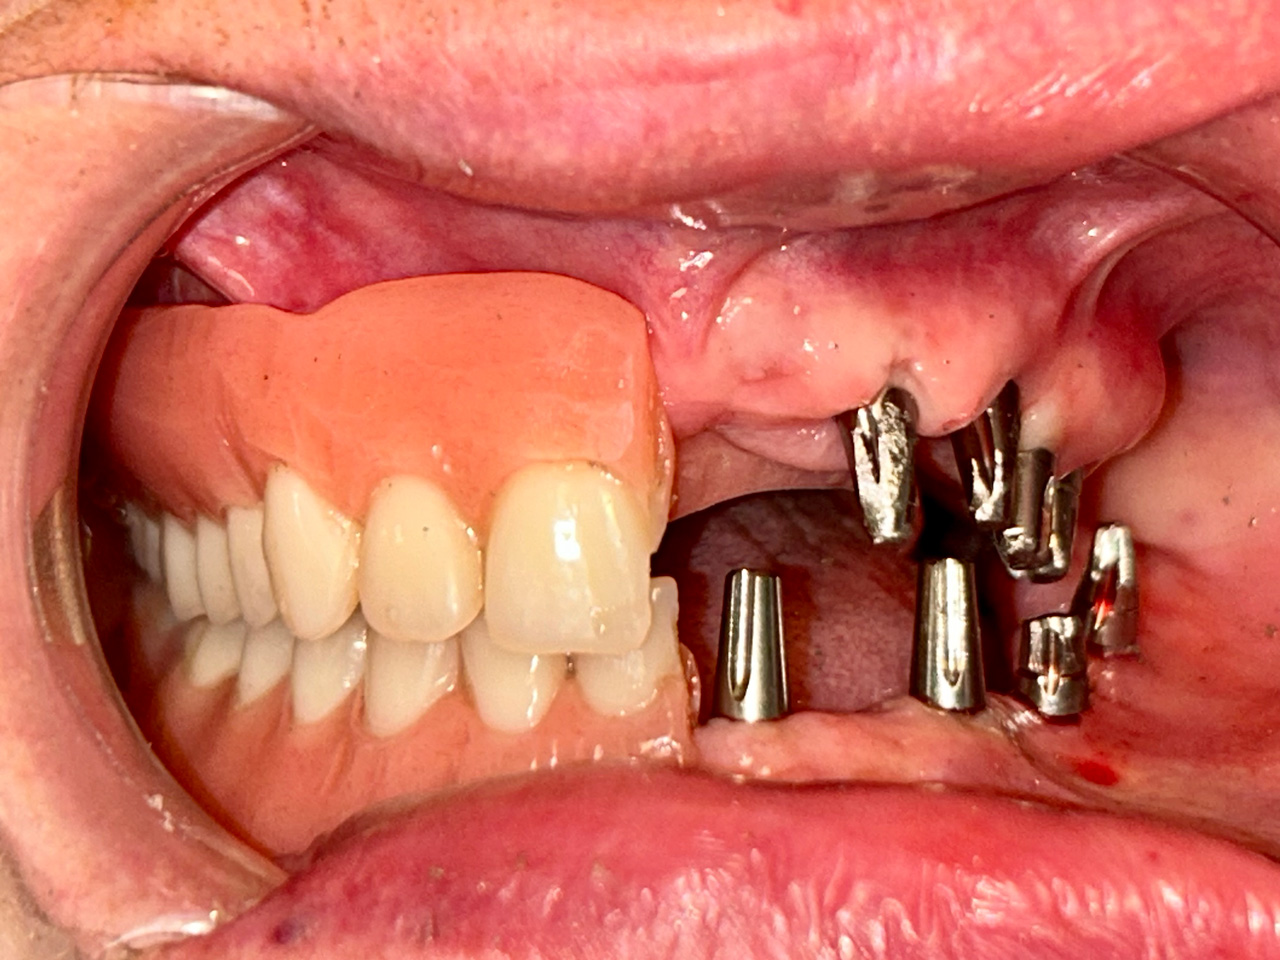

Alsó állcsont teljes rehabilitációja 72 óra alatt

Alsó állcsont teljes rehabilitációja 72 óra alatt, azonnal terhelhető implantátumokkal súlyos paradontitisben szenvedő dohányzó páciens esetében. Az alsó állcsont fogai mind mozogtak az előrehaladott fogágypusztulás miatt.

A fogakat eltávolítottuk, a gyulladt, fertőzött csontot kitakarítottuk, kifertőtlenítettük, majd azonnal implantáltunk.

Svájci, IHDE márkájú, azonnal terhelhető implantátumokat helyzetünk be, és ezekre harmadnapra rögzített, hosszútávú, fémvázas, esztétikus műanyaggal leplezett hidat ragasztottunk be.

Ezt az ideiglenes hidat a sebek gyógyulása miatt használjuk, de tartóssága miatt véglegesként is használható.

A legtöbb esetben, ahogy itt is, 6 hónap múlva porcelán hídra cseréljük, a teljes gyógyulás után.